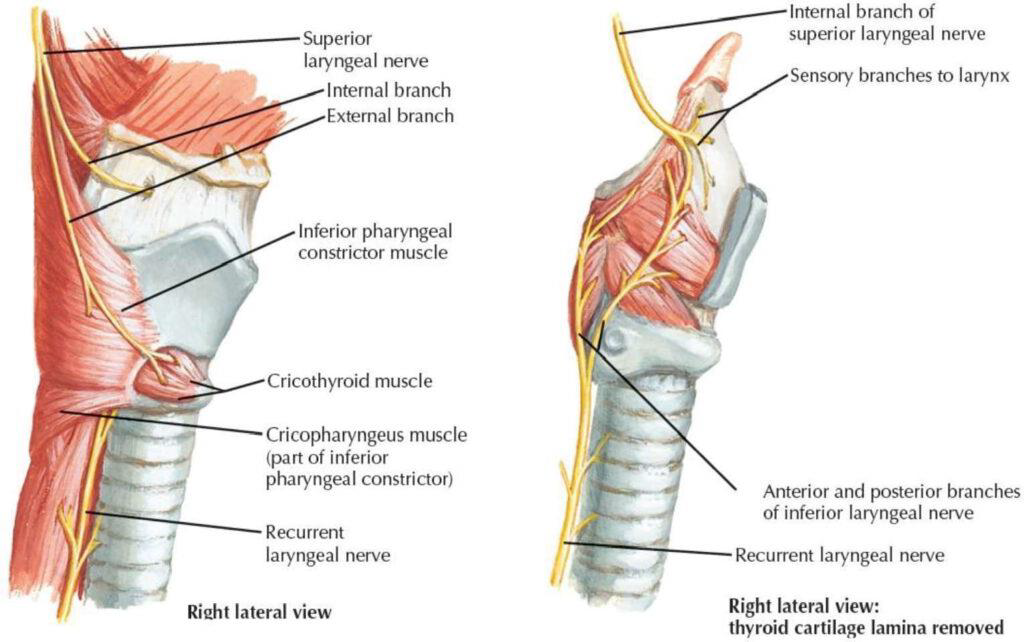

CN X

Structure

- common carotid a. 外側,蓋在 thyrocervical trunk 上

- recurrent laryngeal n.沿 tracheoesophageal groove 攀升(就是食道和氣管中間),接觸 medial thyroid gland,向內鑽到 inf. constrictor,進入 larynx,同時支配感覺與運動

- Sup. laryngeal n.

- Internal br.(Internal laryngeal n.)

- Laryngopharynx

- Larynx (Vocal fold 以上)

- 舌根、Epiglottis 味覺

- External br.

- Cricothyroid m.

- Internal br.(Internal laryngeal n.)

- Recurrent laryngeal n.

- 過Cricothyroid joint改叫Inf. laryngeal n.

- 支配所有軟骨間肌,除了 Cricothyroid m.

- 假聲摺以下的喉部黏膜感覺

recurrent laryngeal n.

- left: arch of aorta

- right: Subclavian a.

Motor: External laryngeal n.

- Cricothyroid m.

- Sup. laryngeal n.

- Internal br.(Internal laryngeal n.)

- Sensor

- 穿過 Thyrohyoid ligament

- External br.

- Motor

- Internal br.(Internal laryngeal n.)

- Recurrent laryngeal n.

- Inf. laryngeal a.伴行

- 過Cricothyroid joint改叫Inf. laryngeal n.